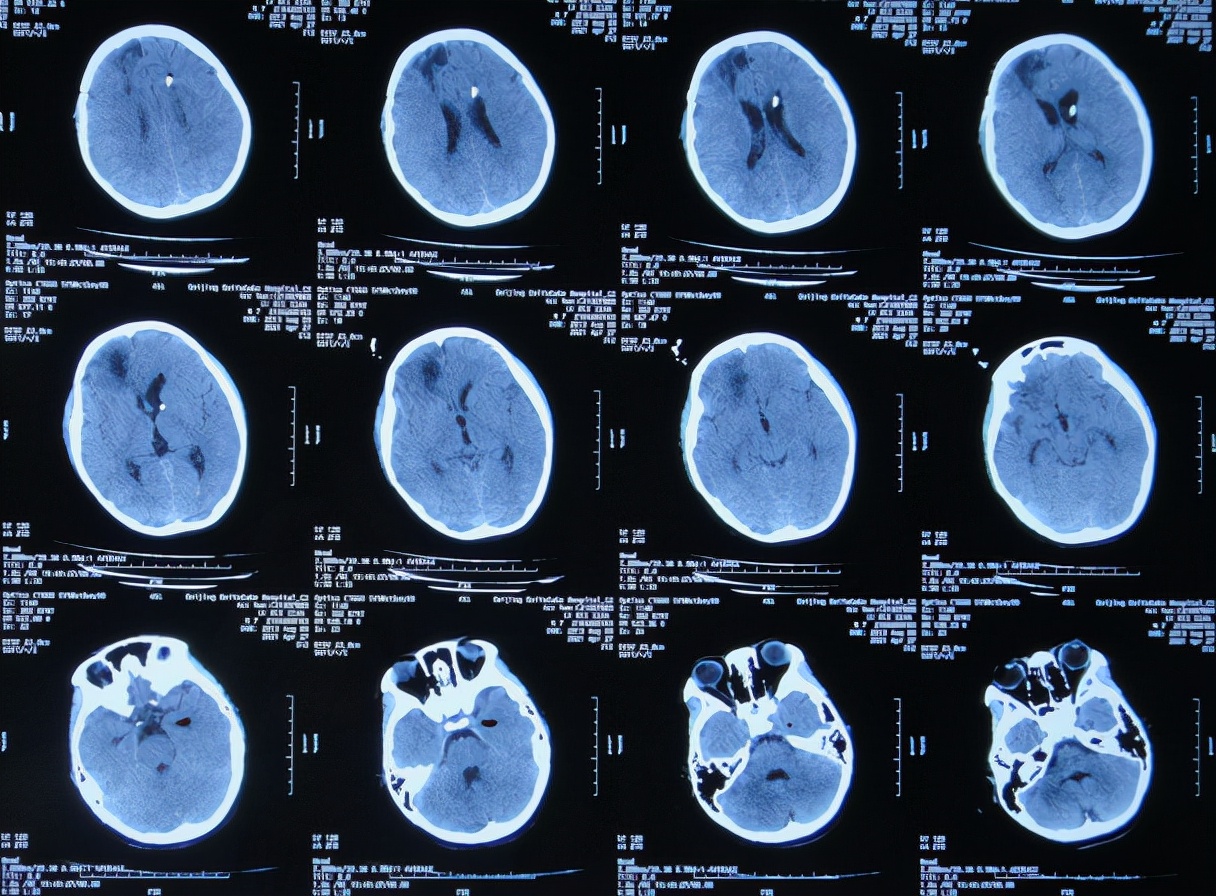

患者2021年3月23日早起突发头痛,意识不清,急送至江苏省徐州市睢宁县某医院,查脑CT示脑出血( 图-1 );既往史有癫痫病史。

图-1: 2021年3月23日脑CT